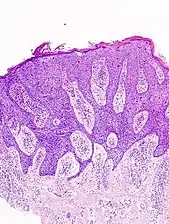

Invasive disease

In invasive SCC, tumor cells infiltrate through the basement membrane. The infiltrate can be somewhat difficult to detect in the early stages of invasion: however, additional indicators such as full thickness epidermal atypia and the involvement of hair follicles can be used to facilitate the diagnosis. Later stages of invasion are characterized by the formation of nests of atypical tumor cells in the dermis, often with a corresponding inflammatory infiltrate.[12]

Superficially invasive squamous cell carcinoma (SCCSI). These lesions often do not show the marked pleomorphism and atypical nuclei of SCC in situ, but demonstrate early keratinocyte invasion of the dermis.[12]